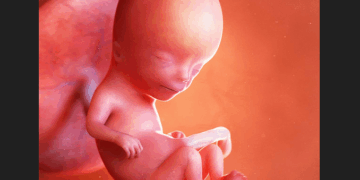

“You really think that this is an image of a human being?” Abortion advocates will often ask this question while showing an image of a dog embryo. (click here to see an example image) If you say yes, the abortion advocate will ruthlessly mock…